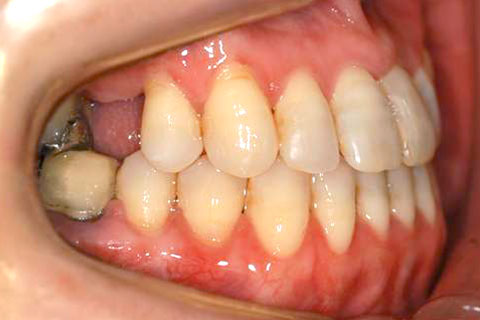

矯正の症例 受け口(反対咬合)

受け口(反対咬合)の症例

症例一覧